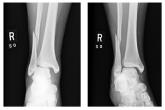

Woman with Severe Ankle Pain After Fall

- Author:

- Nandan Hichkad, PA-C, MMSc

Publish date: February 1, 2011